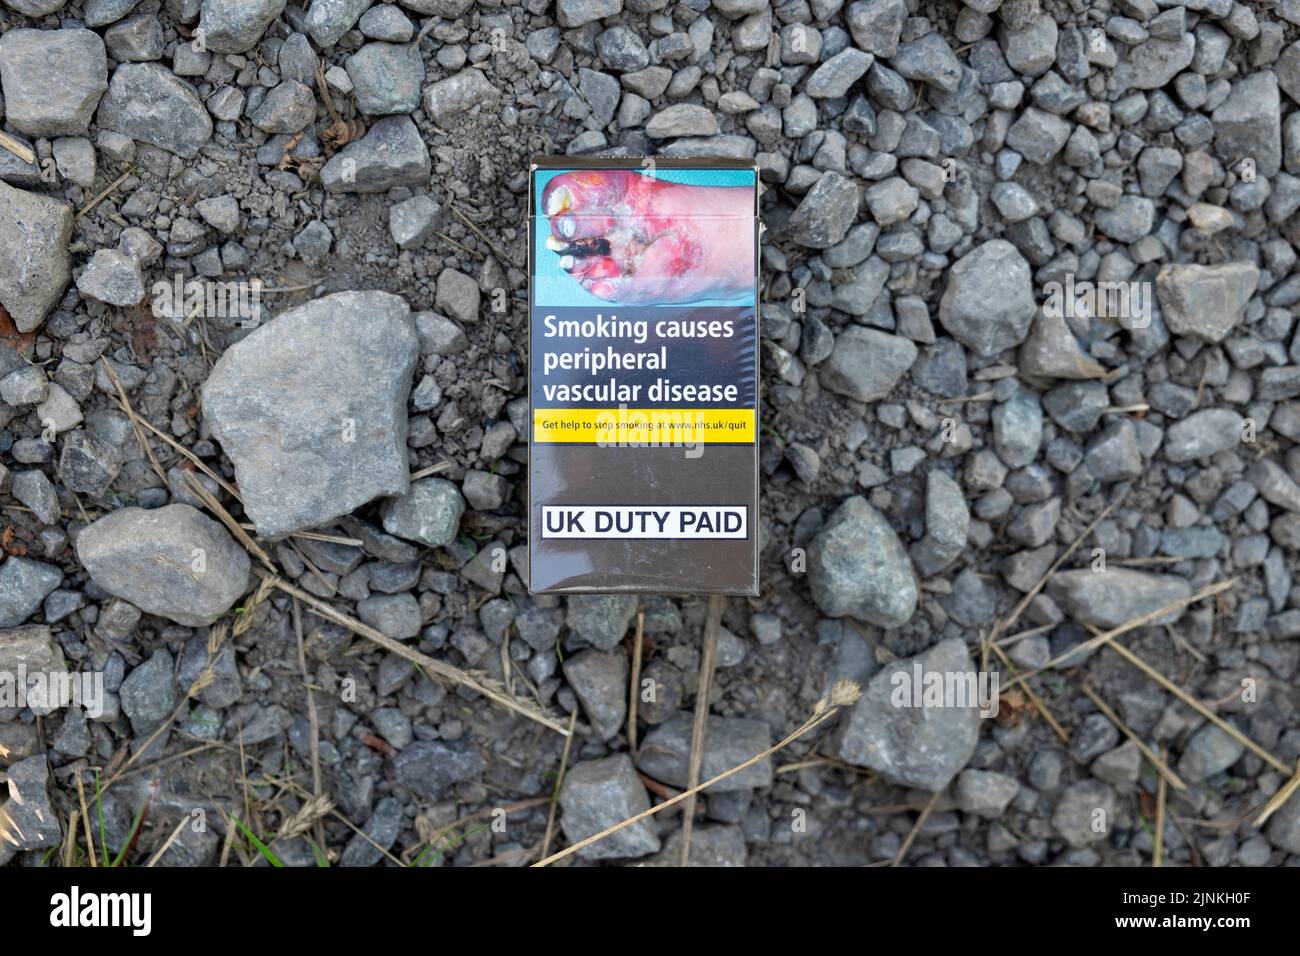

Health warning on cigarette packet pack diseased foot feet warning for smokers 'Smoking causes peripheral vascular disease' Great Britain UK 2022 Stock Photohttps://www.alamy.com/image-license-details/?v=1https://www.alamy.com/health-warning-on-cigarette-packet-pack-diseased-foot-feet-warning-for-smokers-smoking-causes-peripheral-vascular-disease-great-britain-uk-2022-image478018143.html

Health warning on cigarette packet pack diseased foot feet warning for smokers 'Smoking causes peripheral vascular disease' Great Britain UK 2022 Stock Photohttps://www.alamy.com/image-license-details/?v=1https://www.alamy.com/health-warning-on-cigarette-packet-pack-diseased-foot-feet-warning-for-smokers-smoking-causes-peripheral-vascular-disease-great-britain-uk-2022-image478018143.htmlRM2JNKH0F–Health warning on cigarette packet pack diseased foot feet warning for smokers 'Smoking causes peripheral vascular disease' Great Britain UK 2022